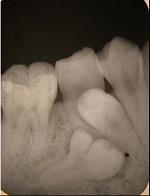

融合牙是 ( ) A.仅见于恒牙 B.两牙牙骨质相连 C.仅见于乳牙 D.两牙牙本质相连 E.两牙牙釉质相连

问题 融合牙是 ( )

选项 A.仅见于恒牙 B.两牙牙骨质相连 C.仅见于乳牙 D.两牙牙本质相连 E.两牙牙釉质相连

答案 D